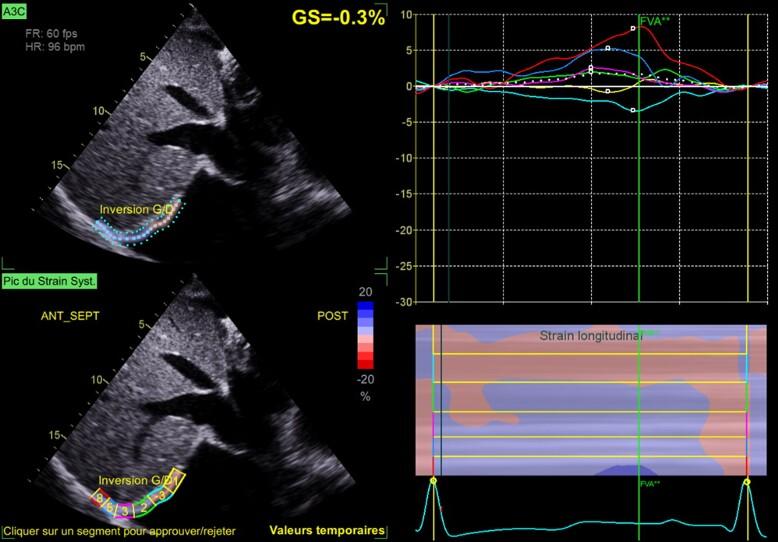

急性心力衰竭中的膈肌超声与膈肌二维斑点追踪成像:病例系列

Diaphragm ultrasound and diaphragmatic 2D speckle tracking imaging in acute heart failure: a case series.

Respiratory muscle function can be affected in patients with heart failure. Ultrasound can be used to assess diaphragm, the main inspiratory muscle. Speckle tracking imaging is an imaging technology providing the evaluation of tissue deformation during contraction. We aimed to evaluate the contribution of traditional echography and 2D speckle tracking imaging in the evaluation and monitoring of patients with acute heart failure (AHF).

CASE SUMMARY

We report a series of four cases of AHF. Diaphragm ultrasound coupled with diaphragm 2D speckle tracking imaging was performed at admission and after decongestive therapy, in cardiac intensive care unit. Patients, at admission, disclosed higher diaphragm 2D strain value and higher diaphragm inspiratory motion value in the context of higher cardiac loading that significantly decrease after decongestive therapy, except for one patient. Diaphragm motion remained less than 10 mm (weakness), despite medical therapy in Cases 2, 3, and 4. Among them, 3 months later, one patient (Case 3) experienced an episode of AHF.

心力衰竭患者的呼吸肌功能可能会受到影响。超声可用于评估主要吸气肌膈肌。斑点追踪成像技术是一种可在组织收缩时评估其变形情况的成像技术。我们旨在评估传统超声心动图和二维斑点追踪成像在急性心力衰竭(AHF)患者评估和监测中的作用。

病例总结

我们报告了4例AHF病例。在心脏重症监护病房,入院时和进行充血性心力衰竭治疗后均进行了膈肌超声检查及膈肌二维斑点追踪成像。患者入院时,在心脏负荷较高的情况下,膈肌二维应变值和膈肌吸气运动值较高,除1例患者外,充血性心力衰竭治疗后这些值显著降低。在病例2、3和4中,尽管进行了药物治疗,但膈肌运动仍小于10毫米(无力)。其中,3个月后,1例患者(病例3)发生了一次AHF发作。